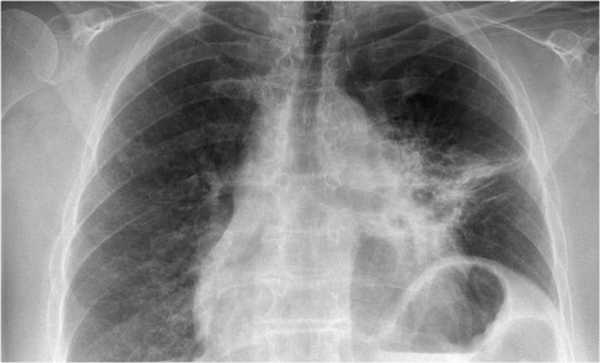

- В левом легком патологические изменения высокой плотности с потерей силуэта контуров сердца.

- Высокое стояние диафрагмы левого легкого.

- Смещение вниз косой щели.

- Низкое расположение правого корня легкого.

Данные изменения характерны при тотальном ателектазе верхней доли левого легкого и частичный ателектаз правого легкого. Так контуры сердца справа хорошо визуализируются то, можно сказать, что частичный ателектаз не средней доли, а нижней доли правого легкого.

Оцените нижележащие ПЭТ/КТ изображения. Легочная карцинома обтурирующая левый верхнедолевой бронх и правый верхнедолевой бронх. Множественные метастазы в кости. Стрелкой указан метастаз в ребро.